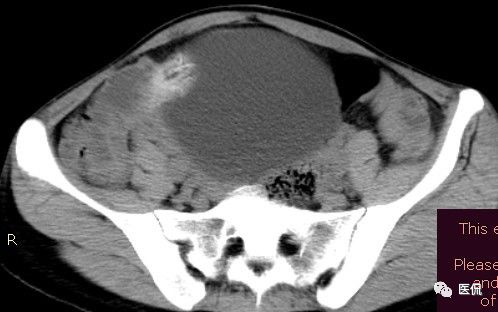

影像特点

腹腔内残留的纱布在人体内引起渗出或液化坏死并纤维包裹形成异物性脓肿(纱布瘤)。纱布瘤的影像特点:圆形或卵圆形肿块,较大,有完整包膜,薄壁,较少的情况下为厚壁,边界较完整,增强后薄膜可以持续强化。不同时期的纱布瘤可以有不同表现:早期(10个月或半年内)多表现为蜂窝状;2~5年内一般表现为囊性飘带状;10~20年之后则为实性软组织密度,包膜钙化呈钙化网状结构。手术过程中残留在人体内的医用纱布所形成的肿瘤样病变。

腹腔内遗留纱布团的影像学表现,以B超较具特征性,其主要表现为:腹腔或盆腔内特殊率减的黑色包块,后方伴有扇形衰减的声影,上窄下宽,好似一“黑色大布”,早期包块内含有不规则光团或光点,随时间延长有缩小或消失,为纱布团内气体。CT的优势在于早期常表现为软组织密度的肿块,其内可见多少不等的气泡,随时间的延长气泡逐渐被吸收减少至消失,增强扫描可见包膜不同程度强化而内容物无强化。熟悉其影像学表现,可在术前作出明确诊断。